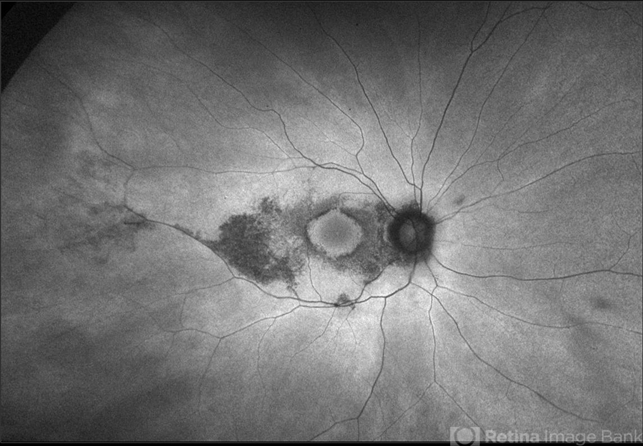

- plaquenil toxicity, ultra-wide field imaging, autofluorescence imaging, fundus autofluorescence (FAF), Optos, focal pigmentary changes, macular edema

- Ultra-wide field fundus autofluorescence photograph of a 60-year-old female with plaquenil toxicity affecting both eyes. Patient was taking plaquenil for management of Lupus, but discontinued use in 2011, but continues to be affected with severe progression of toxicity. Patient developed macular edema affecting her right eye and has received 5 Avastin injections.